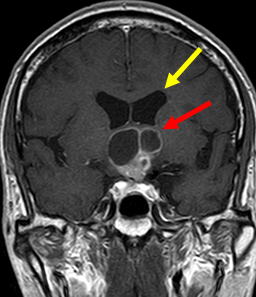

当院で施行された症例をお示しします。60歳男性、仕事でのミスが多くなり、認知症の原因精査のMRIにて、鞍上部に嚢胞を伴う腫瘍像を認め、水頭症も併発していました。(図1-a,b,c)

図1-a正中部に赤矢印の様に嚢胞性腫瘤を認めます。 |

図1-b 黄色矢印の如く脳室拡大も認めます。 |